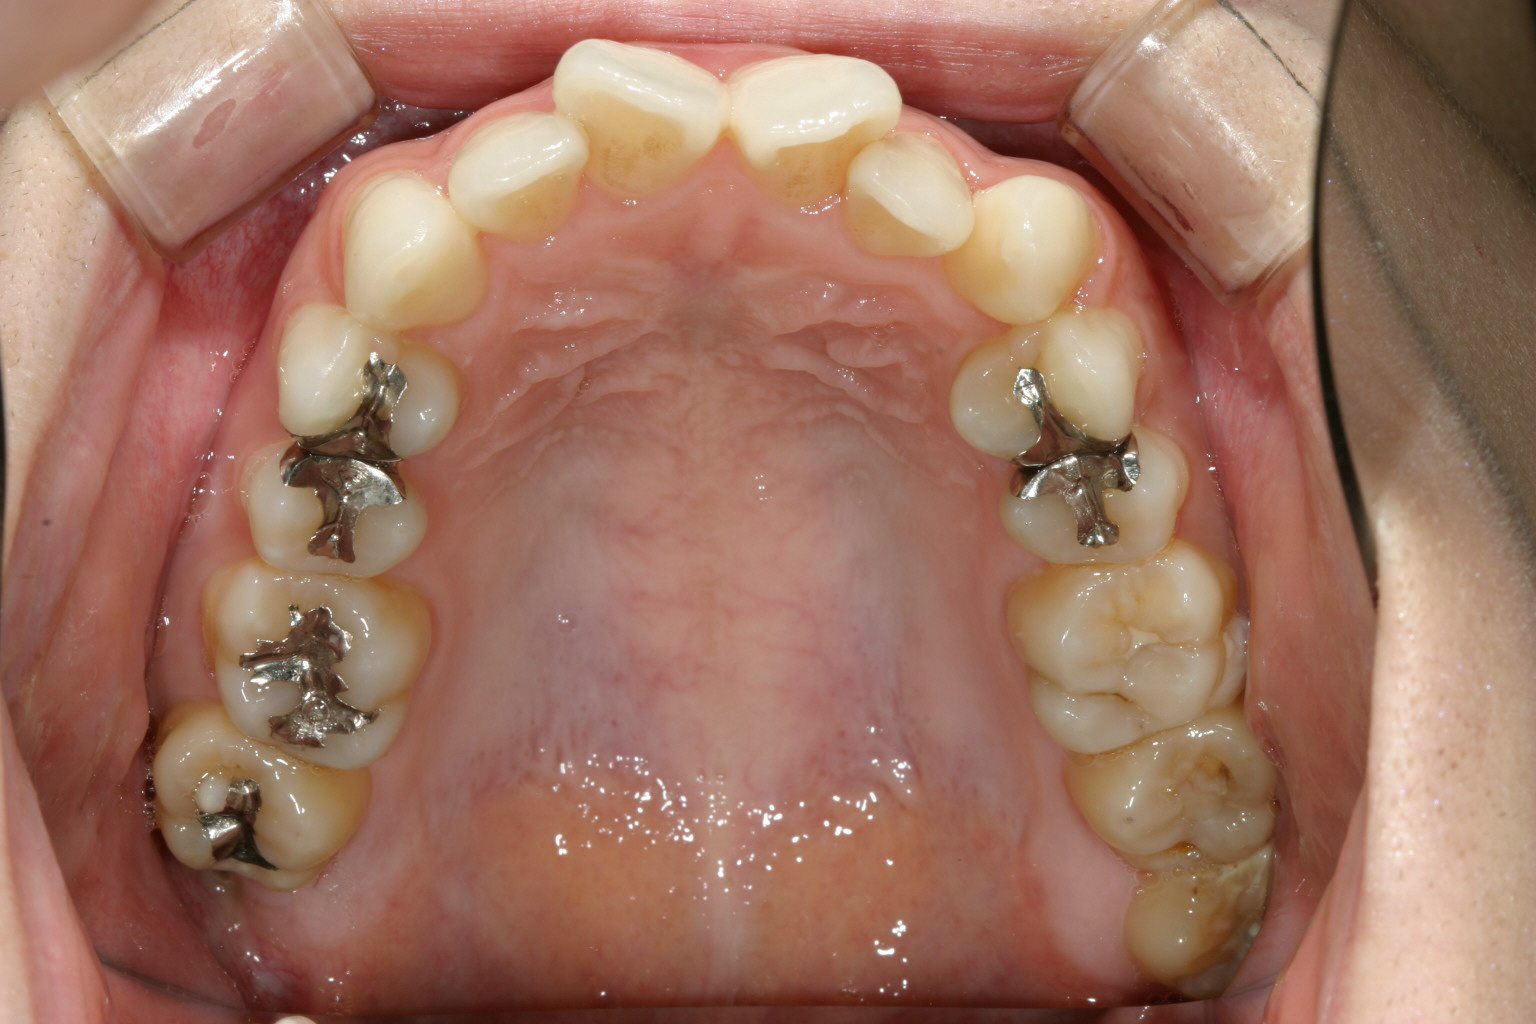

インビザライン初期はこの様な装置でアーチを拡大してからインビザラインを使用していた時期もありました。 現在はこの様な装置は使っていませんが!

特に下顎のアーチが狭い為にクワッドヘリックスって言う装置を使って拡大しています。 現在はインビザラインも進化しこの様な装置を使わずインビザライン単独で拡大できるようになりました。

こちらのケースは当院がインビザラインを導入して初期の頃の症例です。

当時はこの様なアーチの拡大や過度の叢生や翼状捻転がインビザラインだけで改善できるか不安が有りこの様なヘビーな補助装置(クワッドヘリックス)を最初に使ってからインビザラインを使用してました、現在はこの様な違和感の強い装置は使いませんが、、、

インビザラインも年々進化し出来る限り補助装置無しでもかなりの所迄到達出来るようになりました。